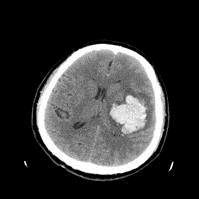

4、什么叫微创手术?

是指利用某些技术,通过较小的伤口和脑组织损伤清除血肿的手术方式。包括:钻孔抽吸、内镜清除

微创手术效果